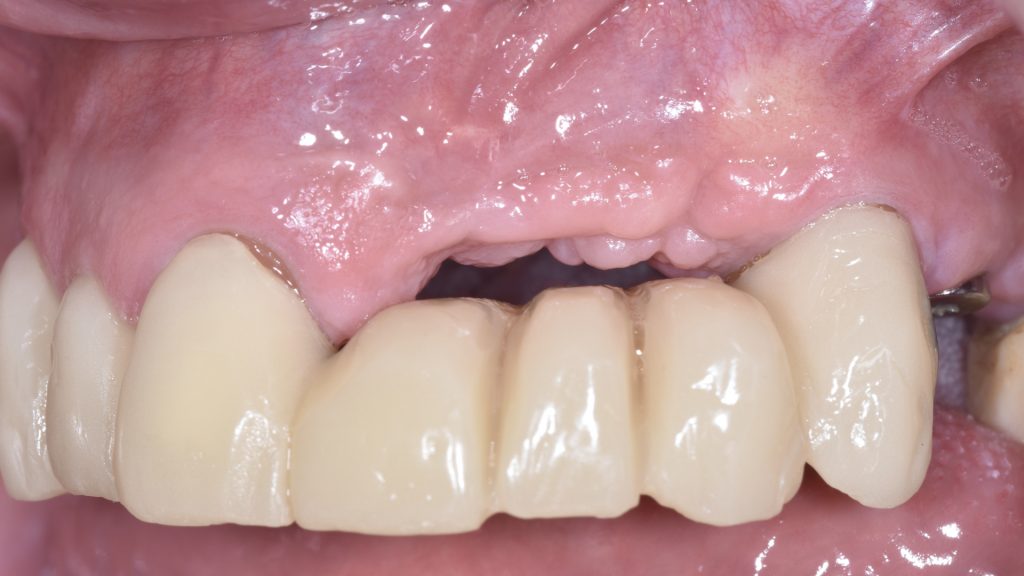

Transcurridos 3 meses tras la segunda intervención se realiza un tercer procedimiento con el objetivo de distribuir homogéneamente el volumen y el tejido en el área tratada.

Finalmente se realiza un tercer procedimiento en el que se realizó un lecho reposicionado apicalmente a espesor parcial y un injerto de tejido conectivo para proporcionar una profundidad de vestíbulo adecuada, distribuir de forma homogénea la cantidad de mucosa queratinizada mejorando el acceso a la higiene y mejorar la calidad del tejido blando para obtener un resultado estético.

Para ello se realiza un colgajo a espesor parcial, se obtiene un nuevo injerto de tejido conectivo de la misma zona palatina y se sutura sobre el lecho.

Este injerto consta de tejido conectivo pero también posee 2mm de epitelio en su parte más coronal con la intención de suturar el colgajo realizado previamente sobre el injerto, dejando expuestos esos 2mm de epitelio en la zona crestal para conseguir un grosor adecuado en la zona crestal y además un resultado estético final más satisfactorio (Figura 13).